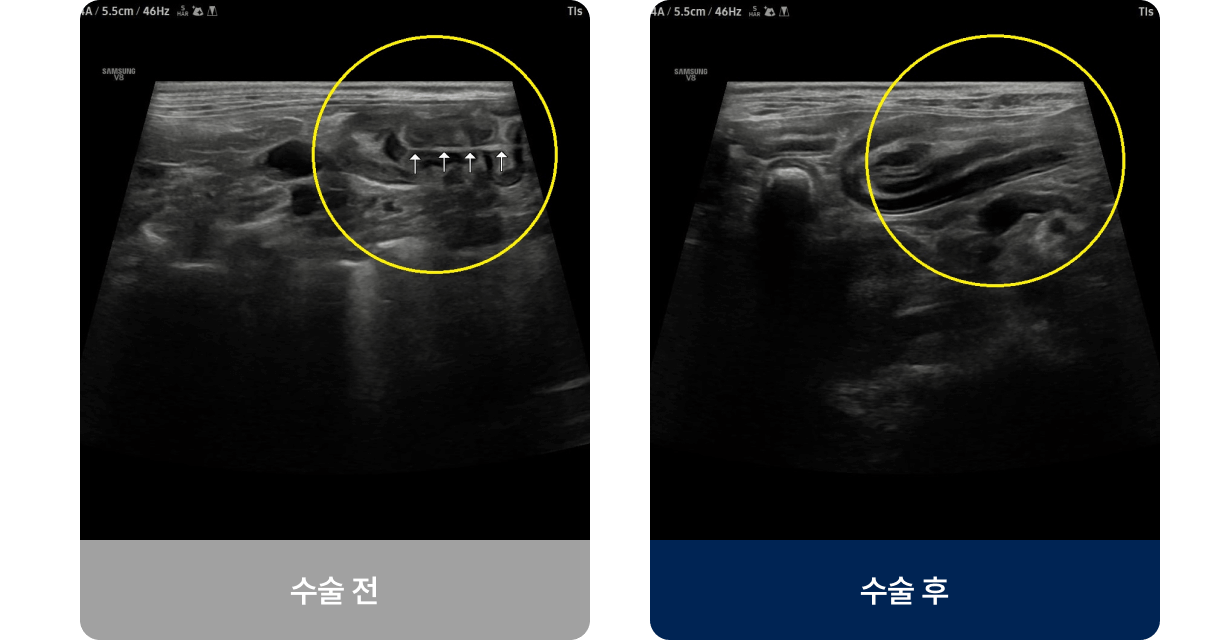

장 속에 이물질(장난감, 뼈, 고무 등)이 걸리거나 종양, 염증 등으로 장의 일부가 막혀 음식물이 통과하지 못하는 상태로, 장 내 순환이 원활하지 못한 경우 탈장 · 복막염 · 장괴사 등 생명을 위협하는 심각한 합병증을 유발할 수 있습니다. 주로 식욕 저하, 구토, 설사 및 대변색의 이상, 복통 증상을 보입니다.

외과적 치료법(수술적 치료)

대상

이물이 크거나 날카로워 배출이 불가능하거나,

장이 완전히 막히거나 괴사·천공 위험이 있는 경우에 시도됩니다.